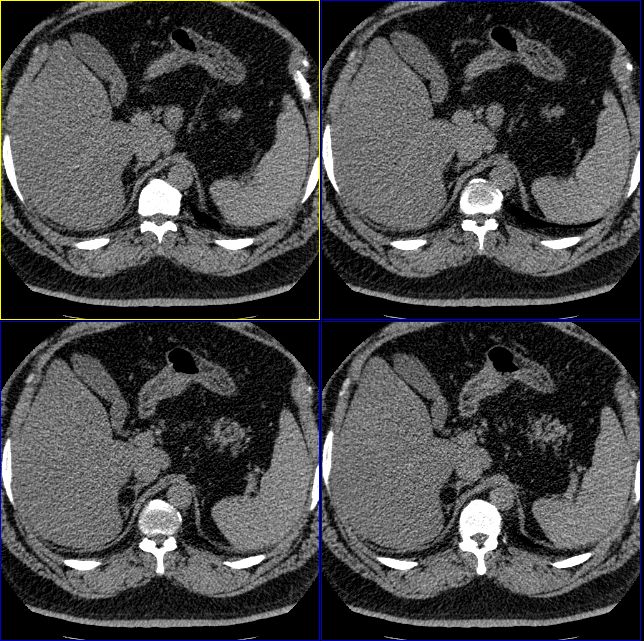

标题: 双侧肾上腺没有问题么?

怎么回事啊,难道肾上腺没有问题么?右侧肾上腺有明显的脂肪性类圆形肿物,左侧也觉得有增生性改变。我们诊断为右肾上腺髓样脂肪瘤,左侧肾上腺增生。大家再仔细看看。

脂肪肝是有的,楼主说的右侧肾上腺囊性灶是不是衬出的假象,密度如何,建议测测

肾上腺很可能有问题,建议矢状位重建,另外结合肾上腺内分泌测定。左侧增生不能除外。

右侧肾上腺好像有一个类圆形的囊性包块,内部密度象是脂肪

1.肾上腺区囊性占位

2.脂肪肝

只能考虑有脂肪肝,至于右侧肾上腺“病变”会不会就是内外支间的脂肪组织?